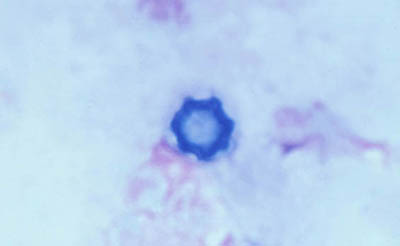

Frotis - extendido en capa

Preparaciones de extendido en capa sobre laminilla con agua destilada sin colorear, en campo claro y bajo contraste de fases: permite buena visualización de las formas Quísticas de Acanthamoeba

Magnificación 160x

Tinción CW

Blanco de Calcofluor + Azul de Evans

Magnificación 160x

Tinción PAS

(Acido Periodico de Schiff)

Magnificación 160x

Magnificación 160x